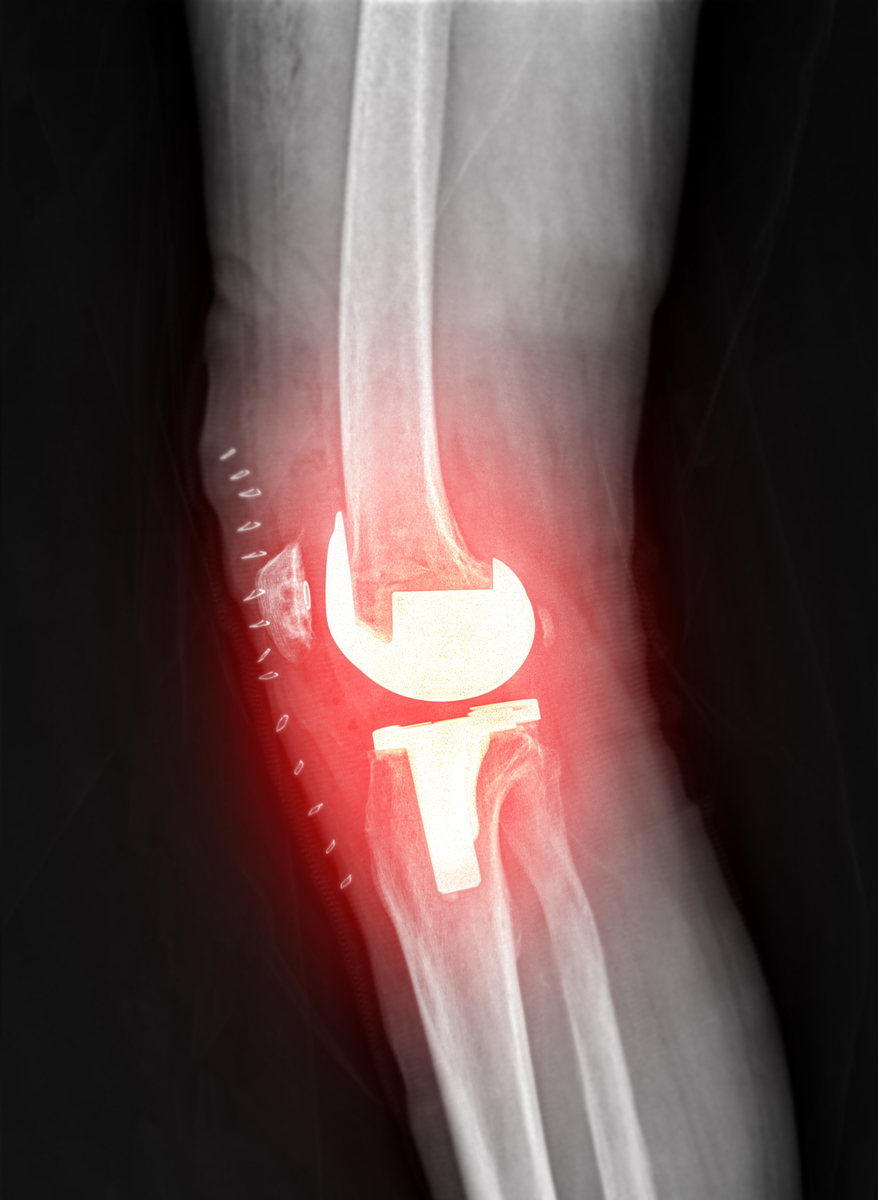

4. 手术治疗:对于严重的膝关节炎,如疼痛不能缓解、关节弯曲或变形等,可能需要进行手术治疗。